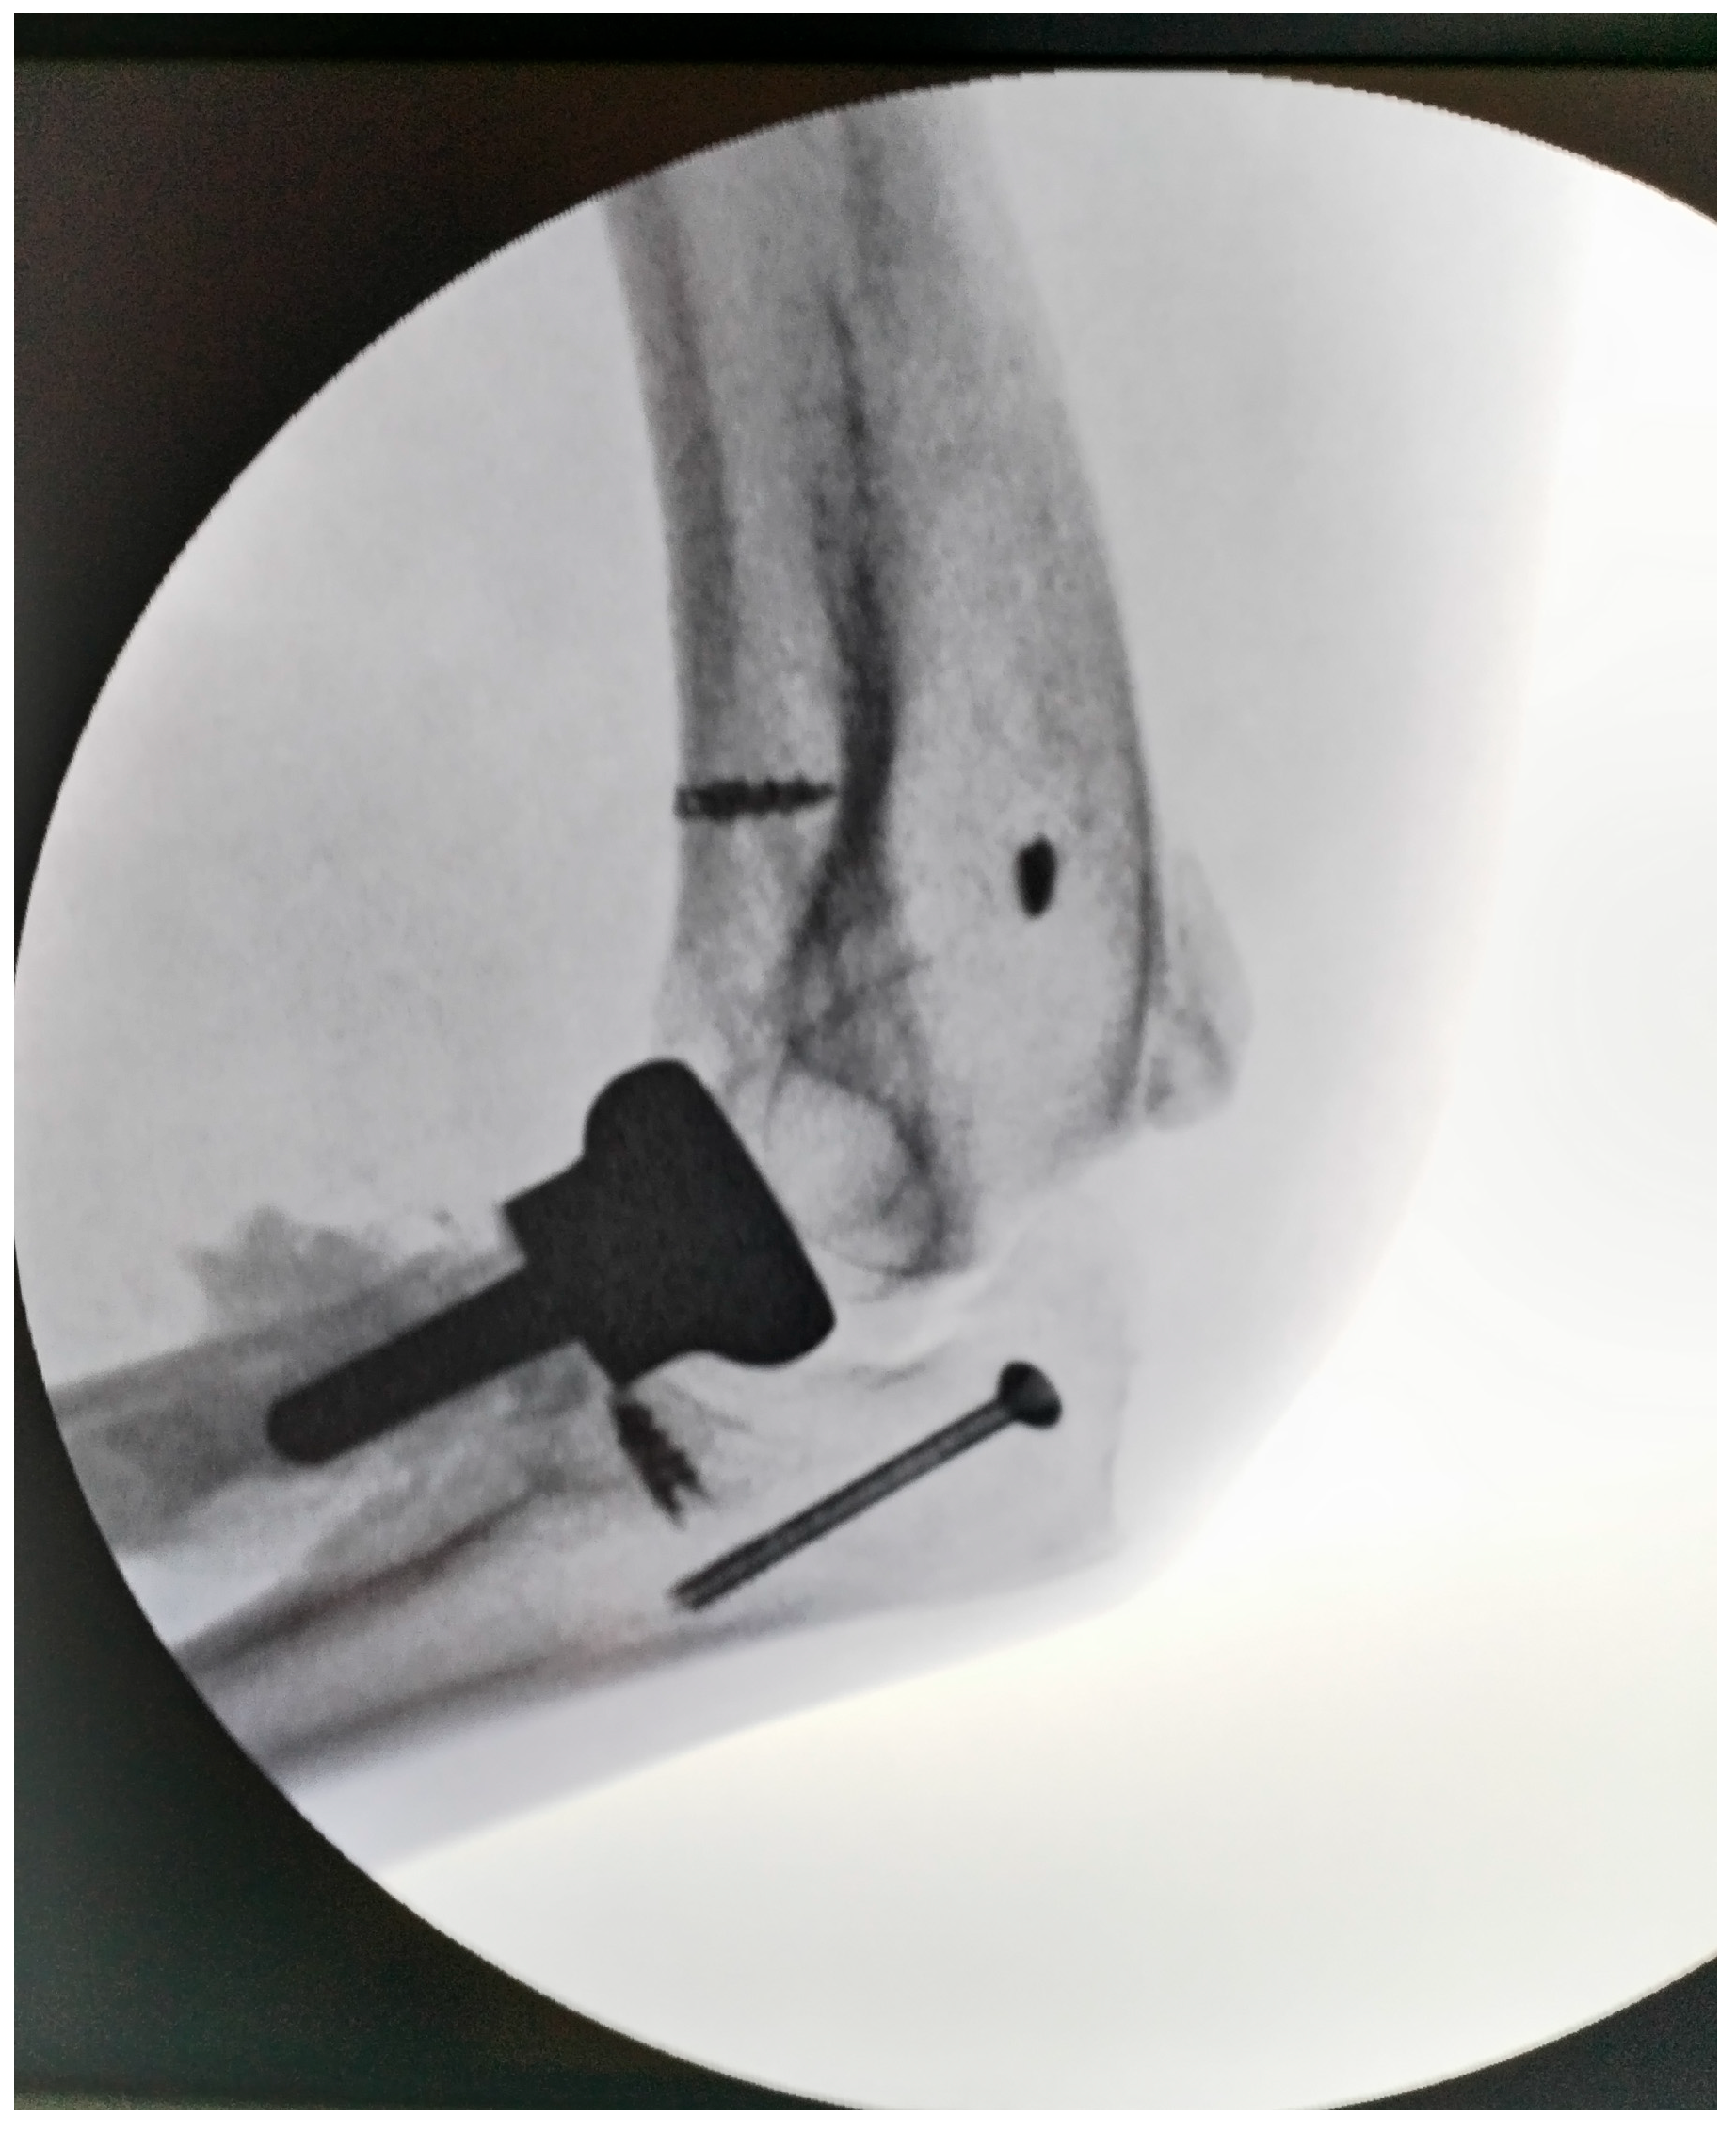

The common extensor tendons were reattached using anchors, and an anterior transposition of the ulnar nerve was performed. Soft tissues were sutured with the elbow positioned at 90° and the radius in pronation, utilizing the prosthetic radial head as a stabilizer. Postoperative radiographs were obtained to confirm proper joint alignment (Figure 4). The wound was closed in a standard fashion over a suction drain to prevent subcutaneous hematoma formation.

Figure 4.

Intraoperative aspect of elbow (radial head arthroplasty and anchors for muscle fixation; the tip of olecranon was stabilized with a cannulated screw).